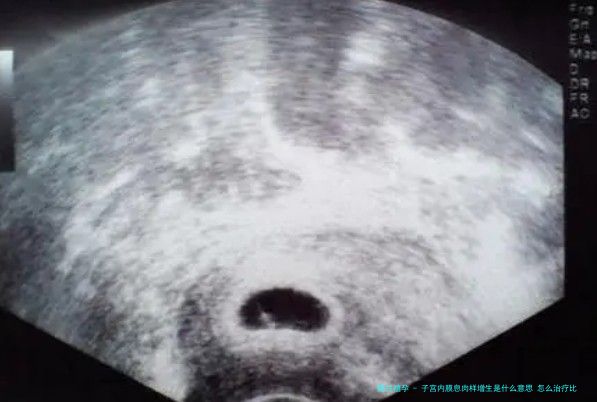

子宫内膜瘜肉样增生便是雌性激素刺激子宫内膜,督促子宫内膜部分增生,末尾凸出子宫内膜轮廓,徐徐组成瘜肉。子宫内膜瘜肉样增生会导致各式各样不良病症,最多见的即是女性阴说出血,经前经后都有流血病症。子宫内膜瘜肉又会导致女性月事失衡,比如月事周期变迁、经量太多或太少。严重者又将会出现阴道炎,导致下体非常不适。

子宫内膜瘜肉样增生又会导致女性不孕不育,因为子宫内膜瘜肉样增生会堵塞输卵管,影响卵子和精子的结合,又会影响子宫内膜部分供血,导致受孕卵没有办法成功着床。子宫内膜瘜肉样增生一朝出现病变还易引起癌症。所以,必须要即时去医院检查治疗。